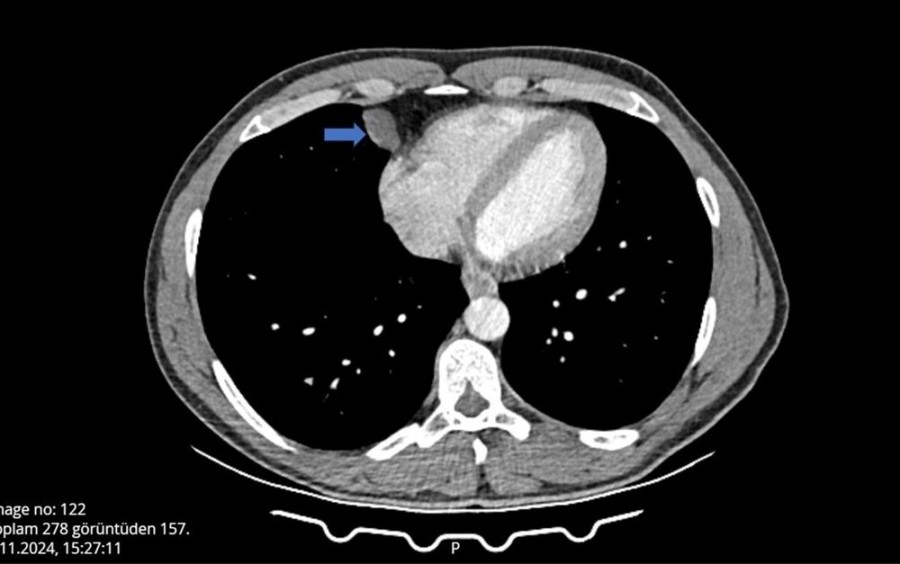

Can, nefes almakta güçlük yaşayınca Şanlıurfa'nın Akçakale ilçesinde hastane aciline başvurdu. Burada tomografisi çekilen Can'ın, akciğer ile kalbinin arasında bir kist olabileceği belirtildi.

Gerekli tetkikleri yapılan Ömer Can'ın, belirtilen bölgesinde yaklaşık 2 santimlik bir kist olduğu tespit edildi ve hemen ameliyata alındı.